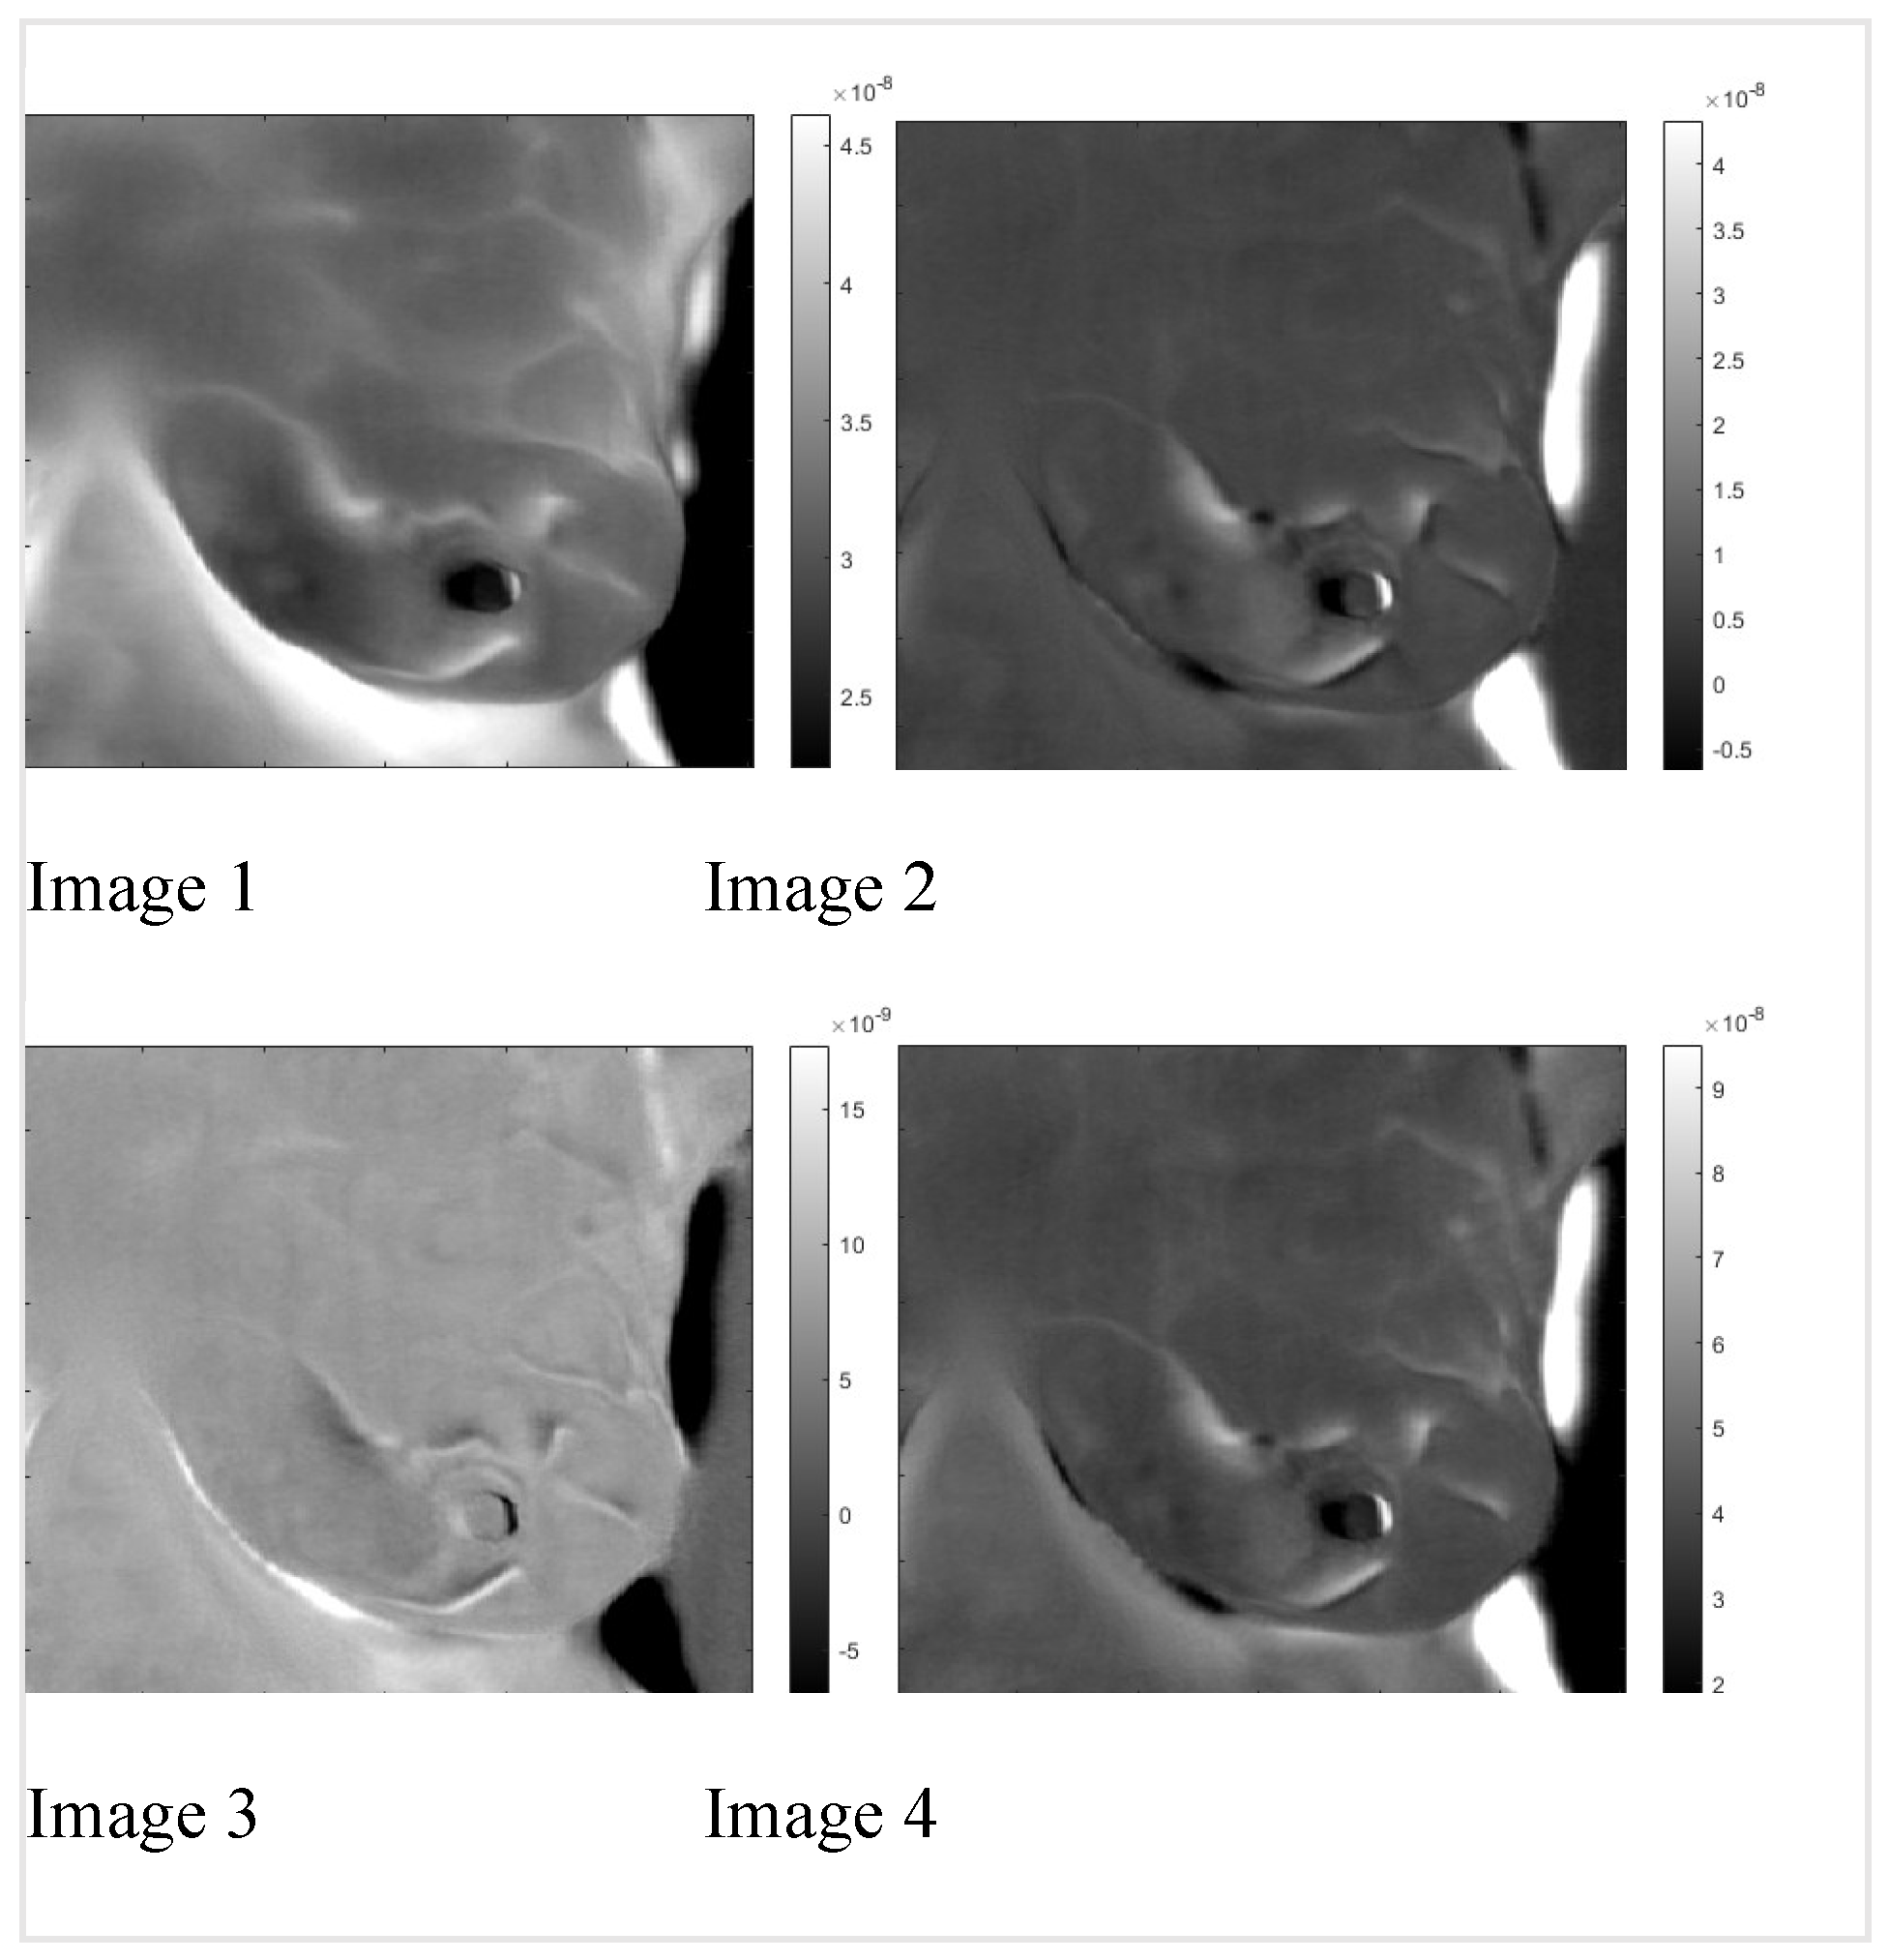

By applying the inverse transformation to the images 2-1 to 2-4, we get the images in Figure 5. In Figure 6, we present the result for the left breast, labeled "sick," and patient #T285 in Figures 7-1 to 7-4 for the left breast, labeled "healthy," and for the right breast, labeled "sick," in Figure 8. The supplemental material presents process images of patients #282 and #286.

Figure 6. Sick left breast of patient “T281.” Images A: to D after application of the inverse PCI transform. A and B are images of thermal reflection, while C and D are images of vasoconstriction.

We identified two very similar thermal images at each breast. The first image is at the same polarity as the external cooling. The second image is from twice the depth of the first one and at the opposite polarity. Our interpretation is: The first reflection is due to vasoconstriction, while the second is due to thermal reflection. Skins nerves trigger vasoconstriction, which results in almost instantaneous constriction. The response to external cooling as a thermal regulation mechanism is the reduction of the heat conduct out of the vascular system, which is at the same polarity as the external cooling. The heat propagates only one way from the vascular system to the skin. Response by thermal reflection is different; the cooling traverses from the skin to the blood vessel, then reaches a constant temperature boundary, blood flow, and propagates back to the skin. The outcome is a signal with the reverse polarity of the cooling at twice the time of the first image. Figures six to eight show reflected heat in images one and three, while images two and four show vasoconstriction-generated signals. Comparing the images of the healthy and sick breast, we notice that the two images of reflection and vasoconstriction of the healthy breast are almost identical; on the other hand, in the sick breast, we can see a difference: Some of the vessels in the vasoconstricted images are not visible or are at reduced intensity; they barely constrict in comparison to a healthy one. We noticed similar behavior in the supplemental images. This reduced constriction might be highly significant as it could be helpful in cancer screening. Remember that the data set had only four image sequences identifying the sick breast.